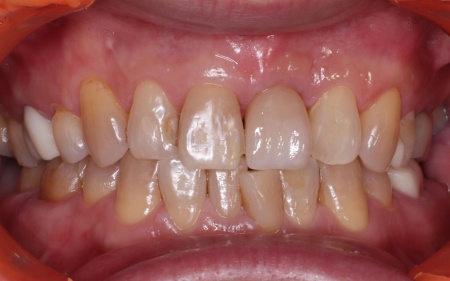

60代女性「一度にすべての歯をきれいにしたい」歯周病や歯の欠損、すきっぱなどを総合的に治療した症例

拝見したところ、部分的に歯周病が確認できました。また、すきっ歯や歯並びがずれている箇所、一部歯がない部分もあり、全体的な治療が必要な状態でした。

歯周病等の基本治療に加え、歯並びを整えるワイヤー矯正、かみ合わせの調整をした上で、欠損していた部分を補うブリッジ治療、インプラントも1箇所行いました。